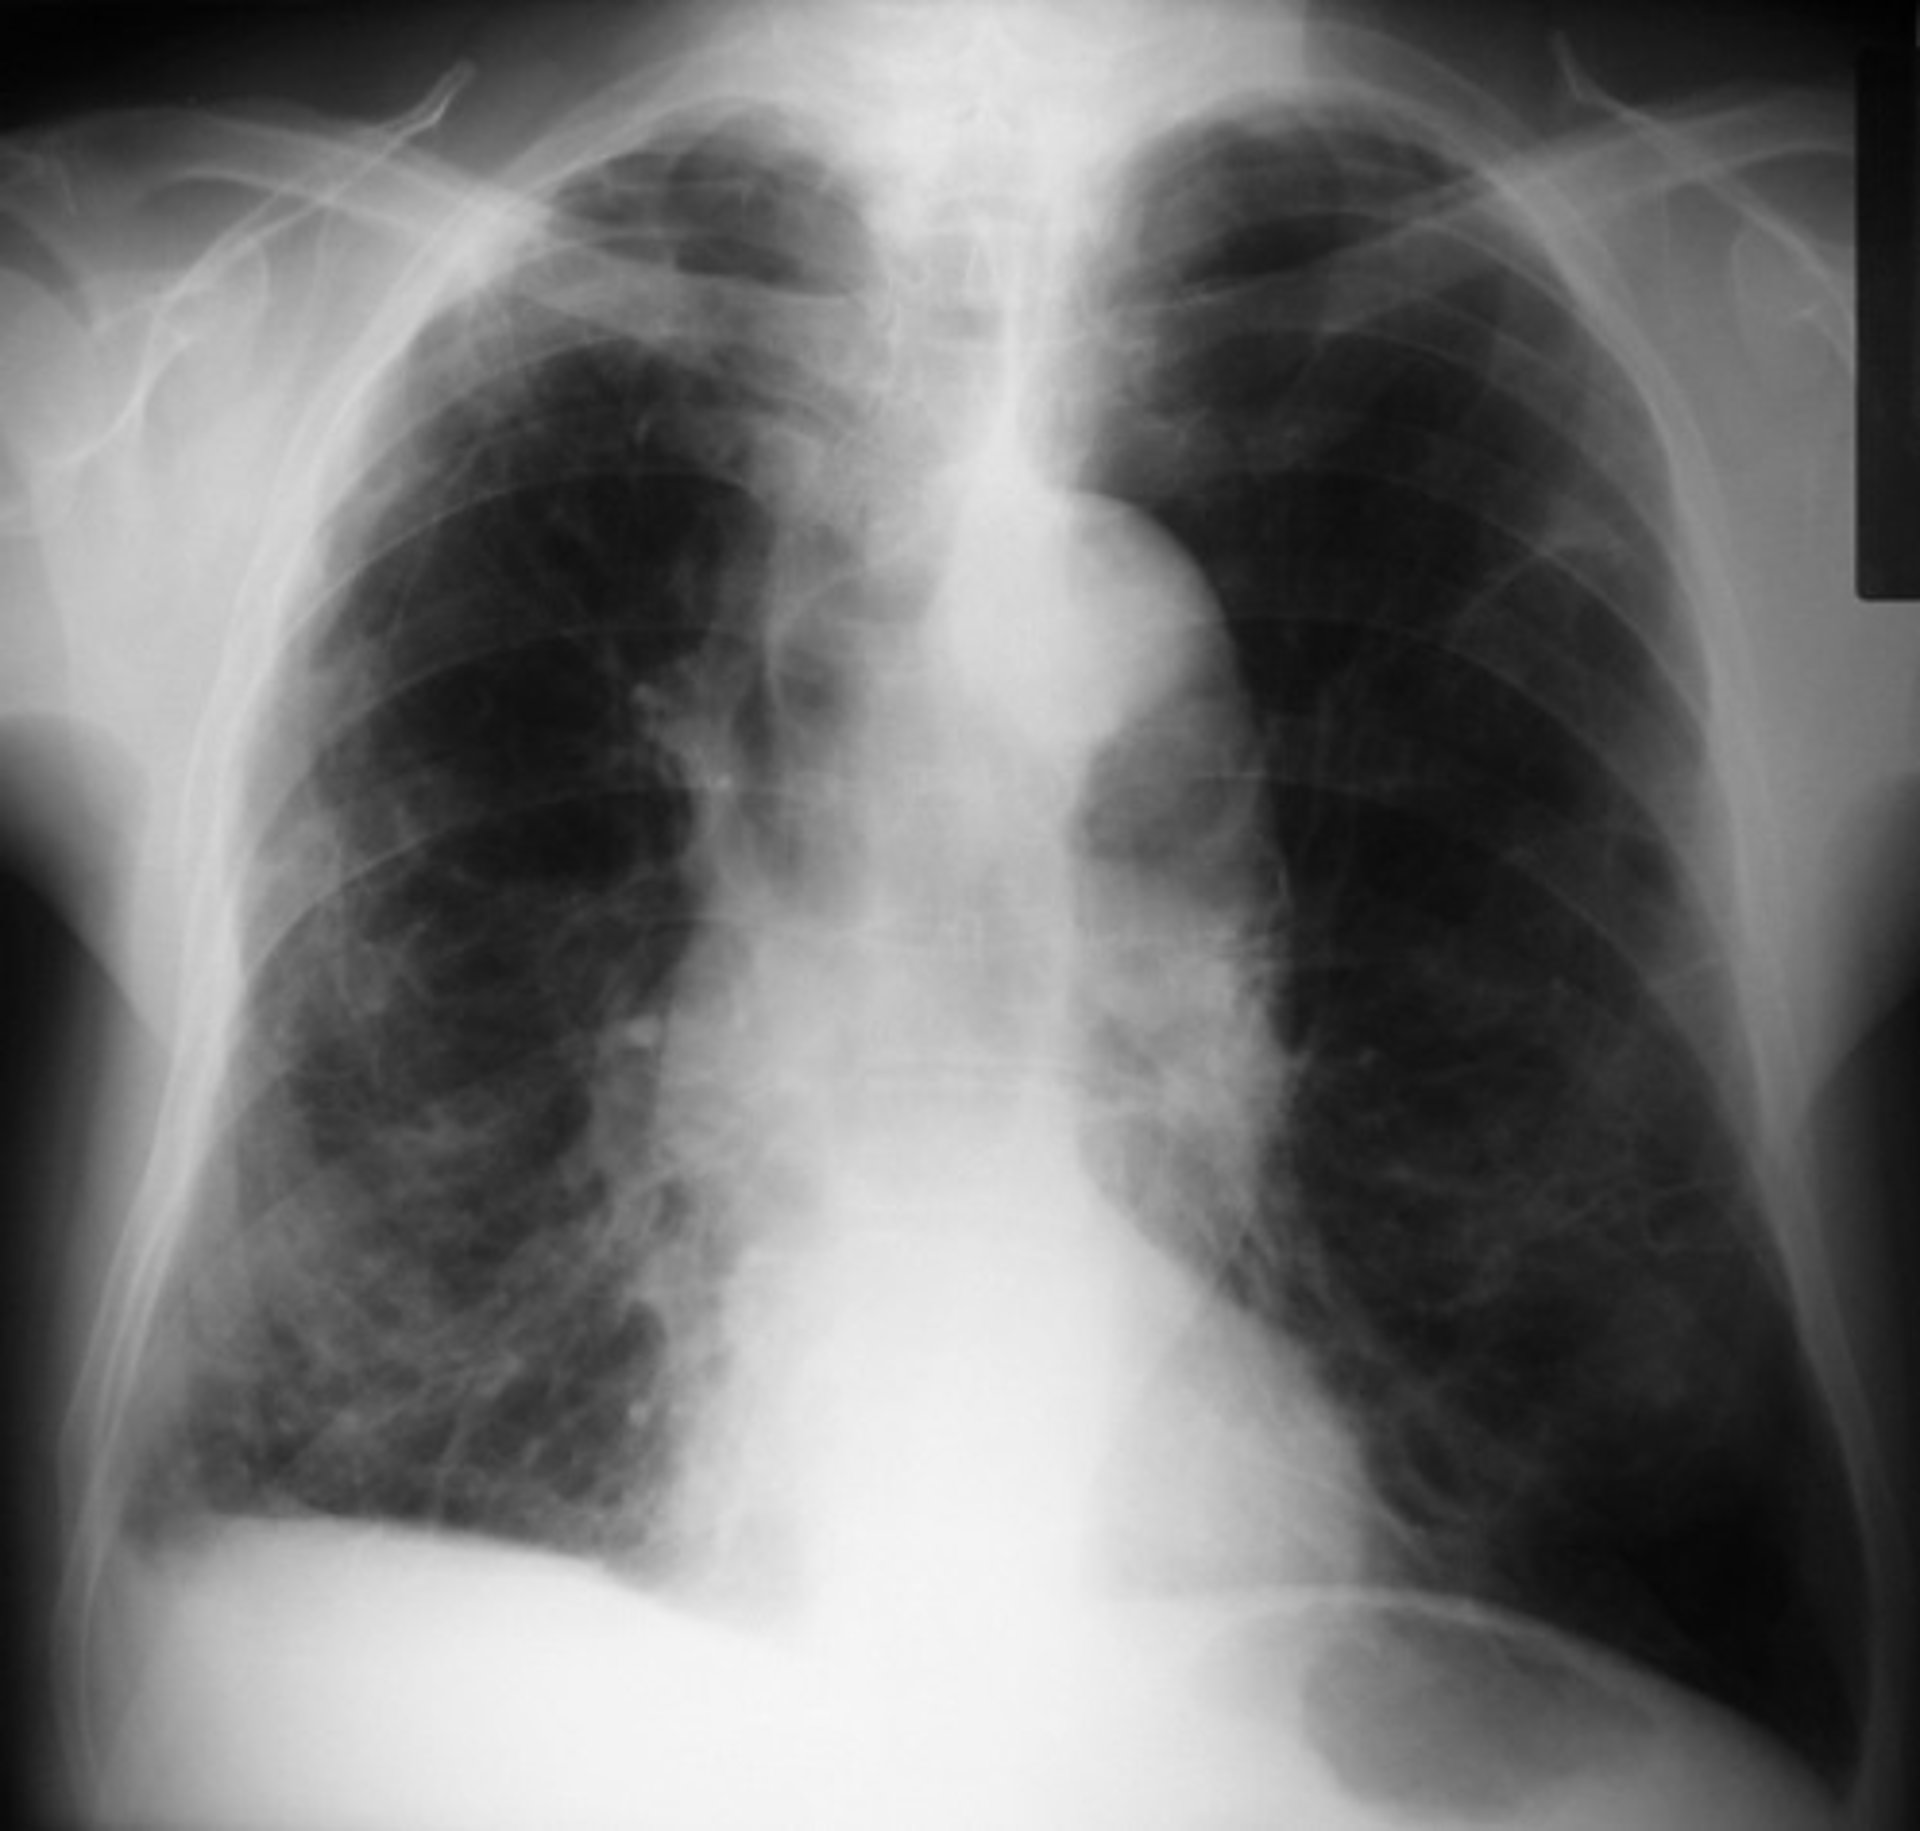

EPOC, una enfermedad desconocida para casi la mitad de pacientes

Entre el 30 y el 40 por ciento de los pacientes con enfermedad pulmonar obstructiva crónica (EPOC) desconoce que padecerla, a pesar de que es la cuarta causa de muerte a nivel mundial y se espera que en unos años represente la tercera, según ha informado a Europa Press el neumólogo y miembro del Área de EPOC de la Sociedad Española de Neumología y Cirugía Torácica (SEPAR), Eduardo Márquez.

Se trata de una patología respiratoria que se caracteriza por una limitación crónica del flujo aéreo producida por el humo del tabaco, que presenta una serie de cambios patológicos en el pulmón y que se asocia con la aparición de otras enfermedades como, por ejemplo, las patologías cardiovasculares, cáncer de pulmón u osteoporosis.